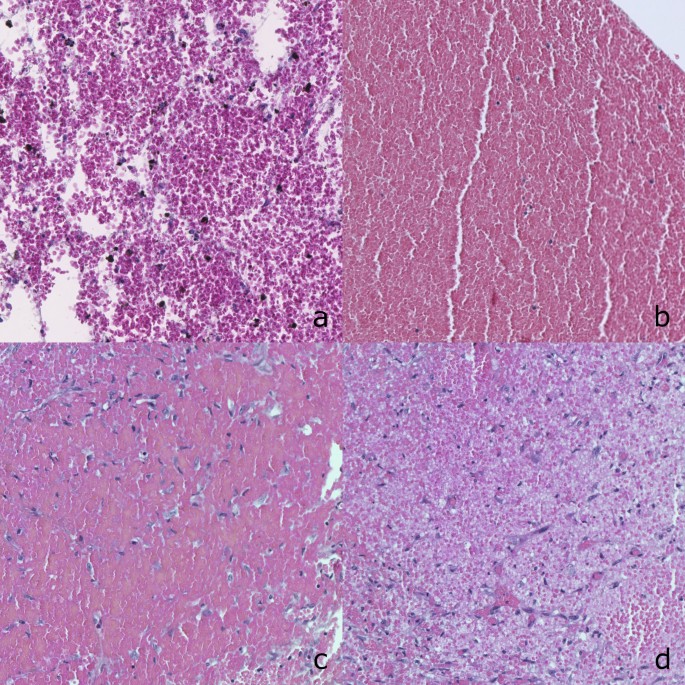

After infant deaths due to non-accidental head injury (NAHI) with subdural hematoma (SDH), the magistrates ask experts to date the traumatic event . To do so, the expert only has tools based on adult series of NAHI . We aimed to develop an SDH dating system applicable to infants aged under 3 years .

Dating is generally done on subdural hematoma (SDH) histopathology [10] . But in few case, the clot or the dura are not present in the seals because of the fluidity of the hematoma or not . . .